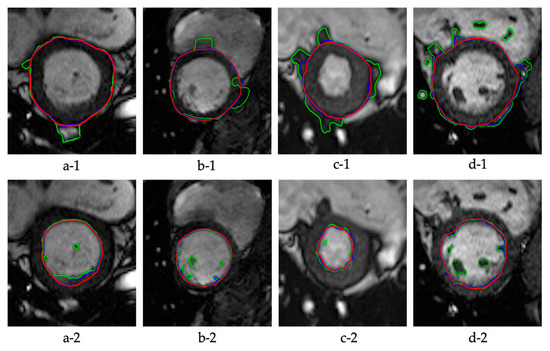

5. Results